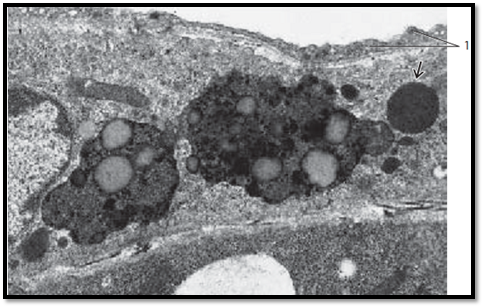

In electron microscopy, lysosomes appear as membrane-enclose d bodies of varied geometry. Their sizes are 0.1–1.2 μm. Before lysosomes participate in intracellular digestive functions, they contain only lysosomal enzymes. At that stage, they are called primary lysosomes or lysosomal transport vesicles . They arise from the trans-face of the Golgi apparatus. Primary lysosomes are able to fuse with phagocytotic vacuoles (phagosomes, autophagosomes, or heterophagosomes , respectively). These vacuoles contain substances, which must be digested. The fusion leads to cytolysosomes ( autophagolysosomes or heterophagolysosomes), commonly called secondary lysosomes . The figure shows two phagolysosomes with many ingested granules and vacuoles with different content. There is also a primary lysosome . Lysosomes are also referred to as the lytic (acid) cell compartment. Pericyte from a capillary.

1 Endothelium of a capillary